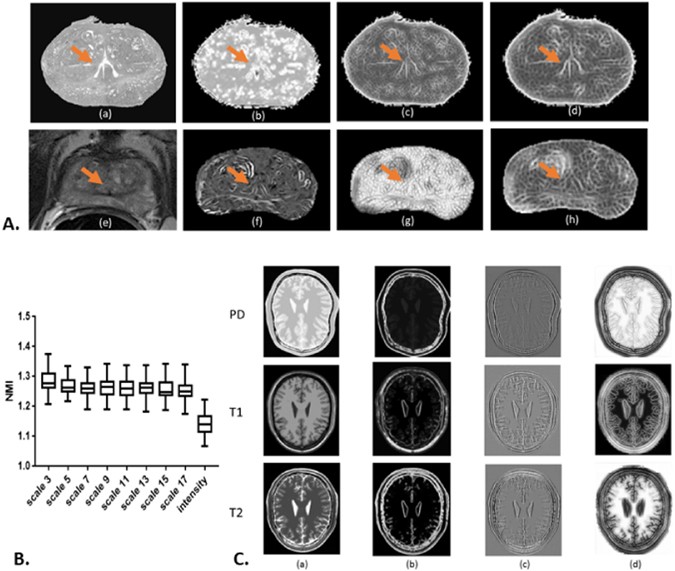

Figure 3 panel B shows a box plot of NMI distribution among 45 pairs of MRI and histology images with original intensity representation and the SE representations with scale κ ∈ {3, 5, 7, 9, 11, 13, 15, 17}. Because each individual scale SE representation consists of 3 SE vectors, we use the average NMI value of these 3 corresponding SE vectors to represent the similarity level between SE representations of MRI and histology images. All the SE representations used in this experiment show greater NMI values than the intensity signal with moderate variance among different scales. The result indicates that SE representations could convert images of different modalities, MRI and histopathology images, to show more substantial similarity compared to the original intensity representation. In addition, SE representations of different scales extract different textural information. In Figure 3 panel A, (a) and (e) are the intensity representations of the moving and fixed images. (b–d) are histopathology SE representations and (f–h) are the corresponding MRI SE representations at scales κ ∈ {3, 11, 17}, respectively. The SE representation at scale κ = 17 shows more similar appearance between the two modalities compared to other image representations. The influence of length scales on morphologic cues within the images is clearly illustrated. For instance, the region corresponding to the urethra is de-emphasized in the representations and at the length scales shown in (b) and (g). On the other hand, (c), (d), (f), and (h) highlight and emphasize the same regions. Panel C demonstrates the intensity representations of brain PD, T1 weighted and T2 weighted MRI in column (a) and SE representations at scale κ ∈ {3, 9, 17} respectively in columns (b)-(d). Similar to the clinical data shown in panel A, SE representations at different scales extract divergent morphology and texture features. Synthetic data SE representations in panel C column (c) illustrate underlying similarities across different modalities compared respectively to columns (a), (b) and (d). These results reinforce our approach, that different morphological structures are emphasized or suppressed across different length scales and only a multi-scale representation can optimally help determine image similarity in order to aid in multimodal co-registration.

In Figure 3 Panel A, sub-panel (a) shows the down-sampled gray scale histopathology image and (e) shows the corresponding T2 weighted MRI slice. (b–d) are SE based representations of histopathology and (f–h) are MRI derived SE representations at scales κ ∈ {3, 11, 17}, respectively. The orange arrows point to the urethra structures. Panel B illustrates the NMI distribution for each scale representation across 45 pairs of histopathology images and MRI. Marked improvement in similarity is observed across all scales and reflected via a greater NMI of SE representations compared to intensity - based representations. In Panel C, column (a) shows the intensity representation of corresponding PD, T1 and T2 MRI and columns (b–d) show their corresponding SE representations at scales κ ∈ {3, 9, 17}, respectively. SE representations across different scales emphasize different attributes in the image, attributes that only become apparent at specific length scales. For instance, for clinical data, the region corresponding to the urethra is de-emphasized in the representations shown in (b) and (g). On the other hand, (c), (d), (f) and (h) highlight and emphasize the same regions. In addition, synthetic data SE representations in Panel C, sub-panel (c) illustrate underlying similarities across different modalities compared to sub-panels (a), (b) and (d).